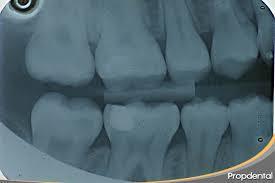

Radiografía Sobre expuesta Los interproximales no se pueden apreciar ya que el cono de la máquina no dirigió los rayos centralizados y cada pieza dental cubre a la adyacente.